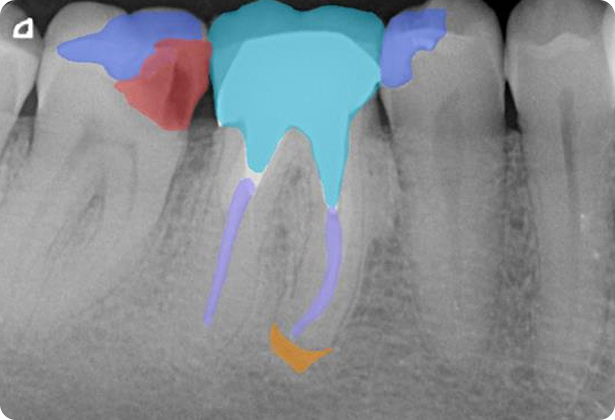

KI-Befunde sind präzise und werden intuitiv in hoher Qualität als farbkodierte Anmerkungen direkt auf dem Röntgenbild und dem interaktiven Zahnschema angezeigt.

Entwickelt, um Sie durch eine fundierte Behandlungsplanung und die Früherkennung pathologischer Befunde von Röntgenaufnahmen zu unterstützen.1